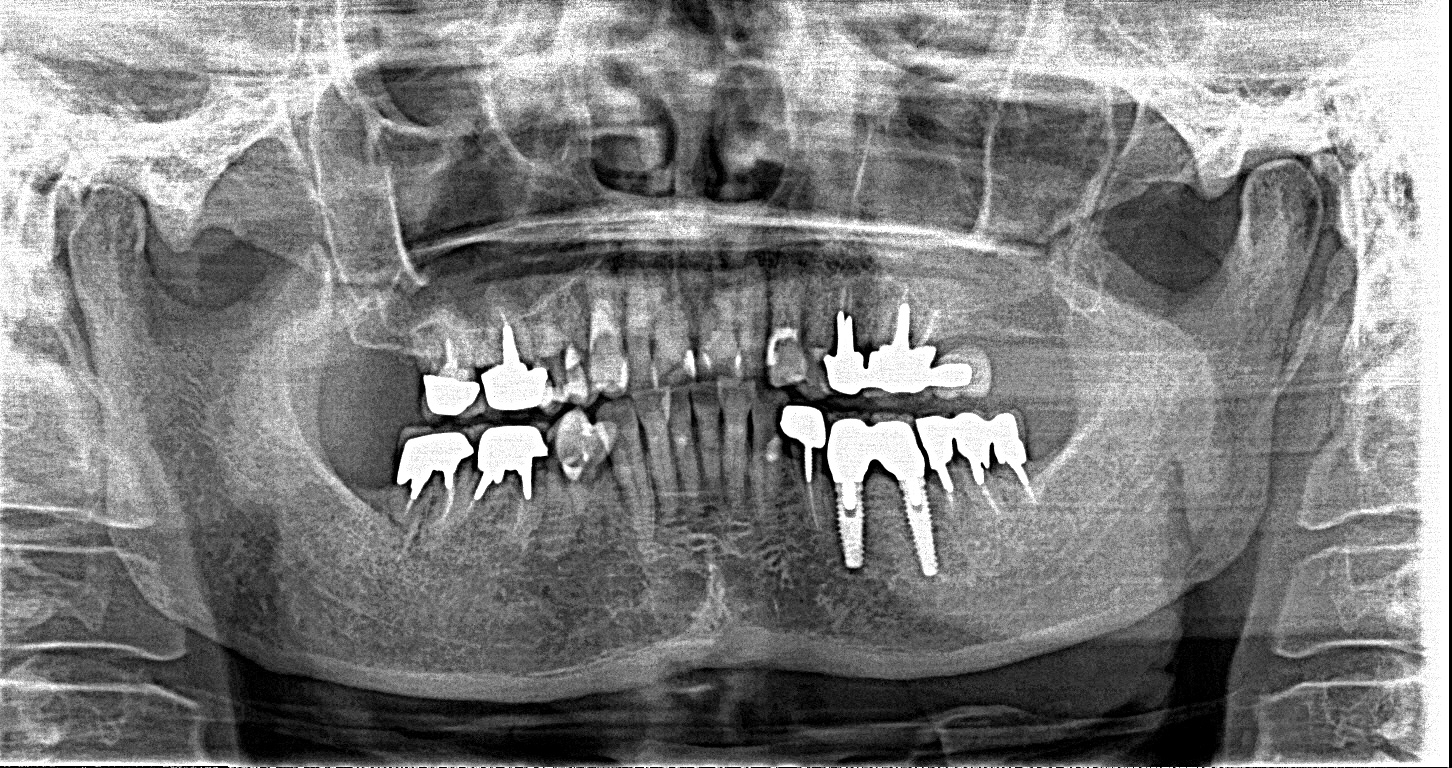

左下567番インプラントジルコニアアバットメント及びジルコニアセラミッククラウン装着